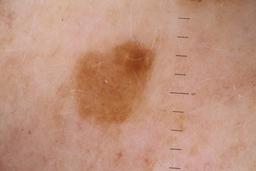

ISIC_5852089

Public

Information

- Created

- Dimensions

- 5184 x 3456

- Attribute to

- Sydney Melanoma Diagnostic Center at Royal Prince Alfred Hospital, Pascale Guitera

- License

- CC-BY-NC

- Used in

- Challenge 2020: Training

- Belongs to

- IP_9124285 IL_2074851

Clinical

| Field | Value |

|---|---|

| acquisition_day | 1173 |

| age_approx | 55 |

| anatom_site_1 | Lower extremity |

| anatom_site_2 | Foot |

| anatom_site_special | acral NOS |

| concomitant_biopsy | False |

| diagnosis_1 | Benign |

| diagnosis_confirm_type | serial imaging showing no change |

| fitzpatrick_skin_type | II |

| image_type | dermoscopic |

| lesion_id | IL_2074851 |

| patient_id | IP_9124285 |

| sex | male |